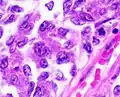

Serous carcinoma

Serous carcinoma is a Type II endometrial tumor that makes up 5–10% of diagnosed endometrial cancer and is common in postmenopausal women with atrophied endometrium and black women. Serous endometrial carcinoma is aggressive and often invades the myometrium and metastasizes within the peritoneum (seen as omental caking) or the lymphatic system. Histologically, it appears with many atypical nuclei, papillary structures, and, in contrast to endometrioid adenocarcinomas, rounded cells instead of columnar cells. Roughly 30% of endometrial serous carcinomas also have psammoma bodies.[20][46] Serous carcinomas spread differently than most other endometrial cancers; they can spread outside the uterus without invading the myometrium.[20]

The genetic mutations seen in serous carcinoma are chromosomal instability and mutations in TP53, an important tumor suppressor gene.[48]

Clear cell carcinoma

Clear cell carcinoma is a Type II endometrial tumor that makes up less than 5% of diagnosed endometrial cancer. Like serous cell carcinoma, it is usually aggressive and carries a poor prognosis. Histologically, it is characterized by the features common to all clear cells: the eponymous clear cytoplasm when H&E stained and visible, distinct cell membranes.[46] The p53 cell signaling system is not active in endometrial clear cell carcinoma.[15] This form of endometrial cancer is more common in postmenopausal women.[20]

Grade 2: >5% and ≤50% solid non-glandular, non-squamous growth.[61] Grade 3: >50% solid non-glandular, non-squamous growth.[61]

Grade 3: >50% solid non-glandular, non-squamous growth.[61] Nuclear grade 1: Oval, mildly enlarged nucleus with evenly distributed chromatin.[62]

Nuclear grade 2: Intermediate features.[62] Nuclear grade 3: Markedly enlarged and pleomorphic nuclei, with coarse chromatin and distinct nucleoli.[62]

Nuclear grade 3: Markedly enlarged and pleomorphic nuclei, with coarse chromatin and distinct nucleoli.[62] Squamous growth seen as necrotic “ghost cells” of keratinocytes at right in image, leaving pink keratin.

Squamous growth seen as necrotic “ghost cells” of keratinocytes at right in image, leaving pink keratin.